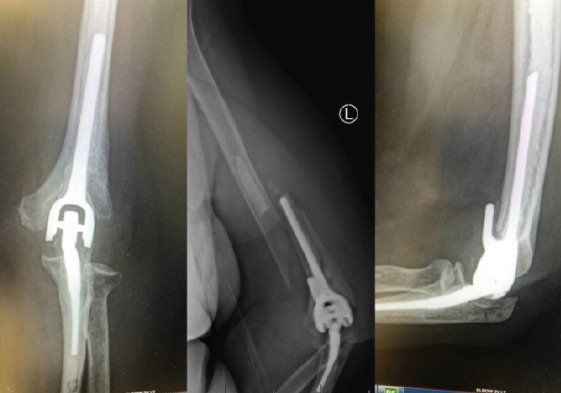

Case report: We present two cases of periprosthetic humerus fractures without implant loosening multiple years after the index procedures. They were treated with open reduction internal fixation (ORIF) utilizing a plate with medial and lateral cortical strut femoral allografting with implant retention.

Conclusion: Two cases of periprosthetic humerus fractures about total elbow arthroplasties were successfully treated with ORIF with medial and lateral cortical strut augmentation. Treatment for periprosthetic elbow fractures should be tailored to each patient based on factors, such as stability of implant, bone stock, and patient goals.